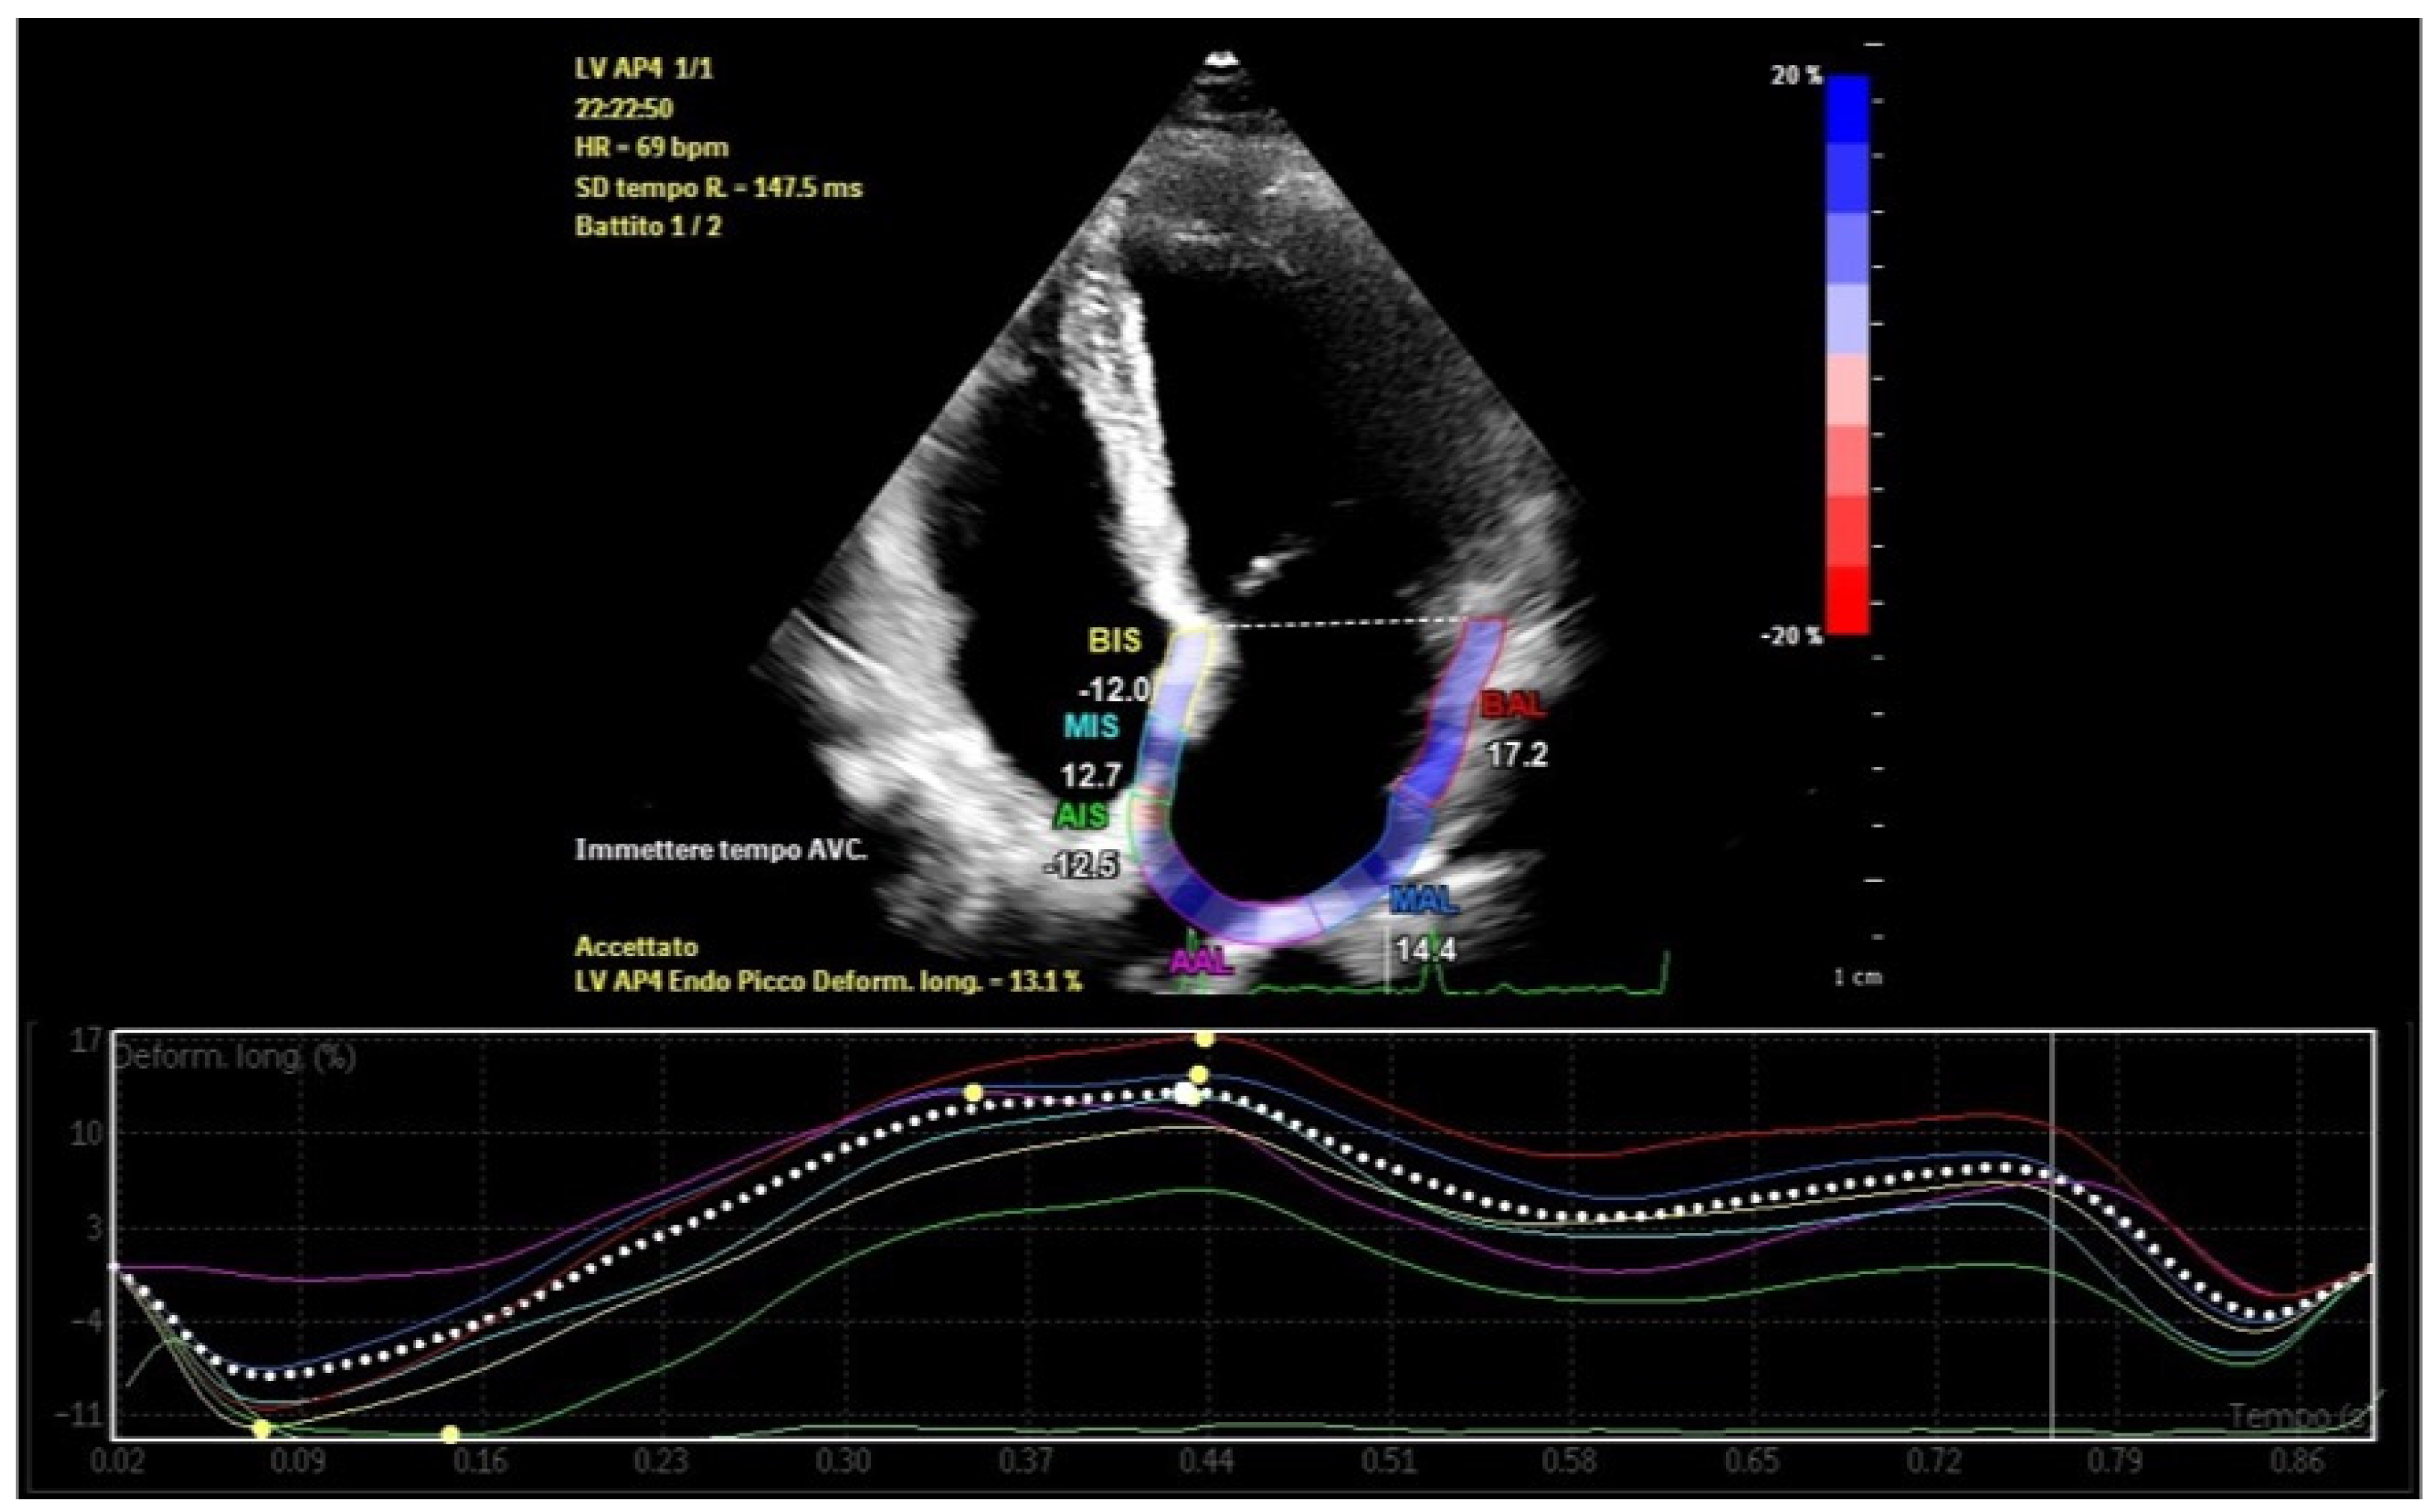

Left atrial strain, measured using speckle-tracking echocardiography, has emerged as a valuable tool for non-invasive assessment of atrial function. This technique evaluates myocardial deformation, dividing the imaging results into three phases: reservoir strain, conduit strain, and booster strain (Figure 1) [8]. Strain imaging enables early detection of atrial dysfunction before structural abnormalities become apparent, facilitating timely intervention and risk stratification [9]. This review examines the interplay between LA-EAT and atrial remodeling, emphasizing the clinical utility of atrial strain analysis in screening, management, and prognosis.

Figure 1.

Phases of left atrial strain in a healthy subject.

Atrial strain, assessed via speckle-tracking echocardiography, quantifies myocardial deformation and provides insights into atrial reservoir and contractile functions [23]. This technique allows early detection of subtle atrial dysfunction, even before structural abnormalities manifest [24]. Strain imaging also identifies and quantifies atrial dyssynchrony, which reflects temporal discrepancies in atrial deformation during the cardiac cycle (Figure 3) [25,26].

Figure 3.

Left atrial strain showing dyssynchrony in a patient with recurrent episodes of paroxysmal atrial fibrillation and abundant left atrial epicardial adipose tissue.